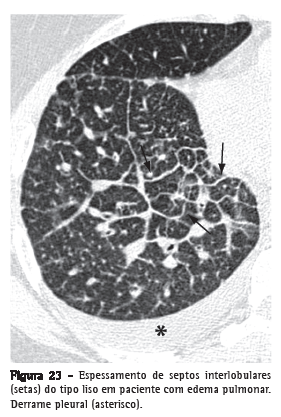

Espessamento de septos interlobularesEspessamento dos septos de tecido conjuntivo que separam os lóbulos pulmonares secundários. Caracterizado na radiografia por finas opacidades lineares, também denominadas de linhas B de Kerley.

Usualmente encontra-se em íntimo contato com a superfície pleural lateral, junto aos seios costofrênicos, apresentando um ângulo reto em relação à parede. Atualmente os termos "linhas septais" ou "espessamento septal" têm sido preferidos ao invés de linhas de Kerley. Na TCAR (Figura 23), o espessamento dos septos interlobulares é caracterizado pela presença de opacidades lineares que delimitam os lóbulos pulmonares secundários, mais facilmente caracterizável na região subpleural, onde tem aspecto de linhas perpendiculares à superfície pleural.(3,44) Nas regiões centrais dos pulmões, o espessamento dos septos de lóbulos adjacentes resulta no aspecto de arcadas poligonais. O espessamento septal pode ser secundário à alteração de qualquer um de seus componentes (veias, vasos linfáticos ou tecido conectivo) e é um achado comum a várias alterações pulmonares, embora sua presença seja particularmente destacada nos casos de edema pulmonar e de linfangite carcinomatosa. O espessamento septal pode ser do tipo liso (Figura 23), nodular (Figura 24) ou irregular. Essa diferenciação pode ajudar no diagnóstico diferencial das diversas etiologias.